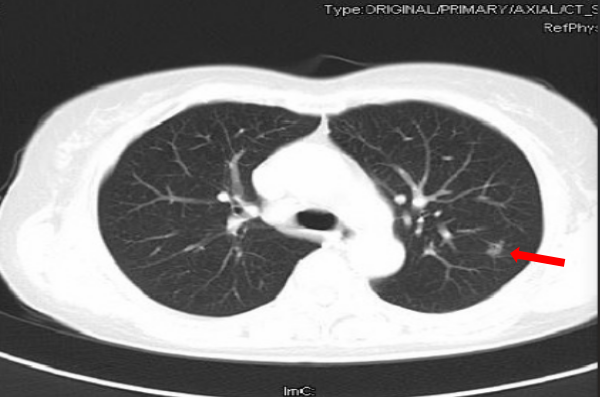

1、单纯性与混合性GGO

单纯性或者完全性GGO是指病灶内无实性成分的病灶,在影像学上表现为完全的均匀的云雾状结节。而混合性GGO则是含有部分实性组织成分的病灶,类似荷包蛋状。

图二 单纯性与混合性GGO影像学表现对比